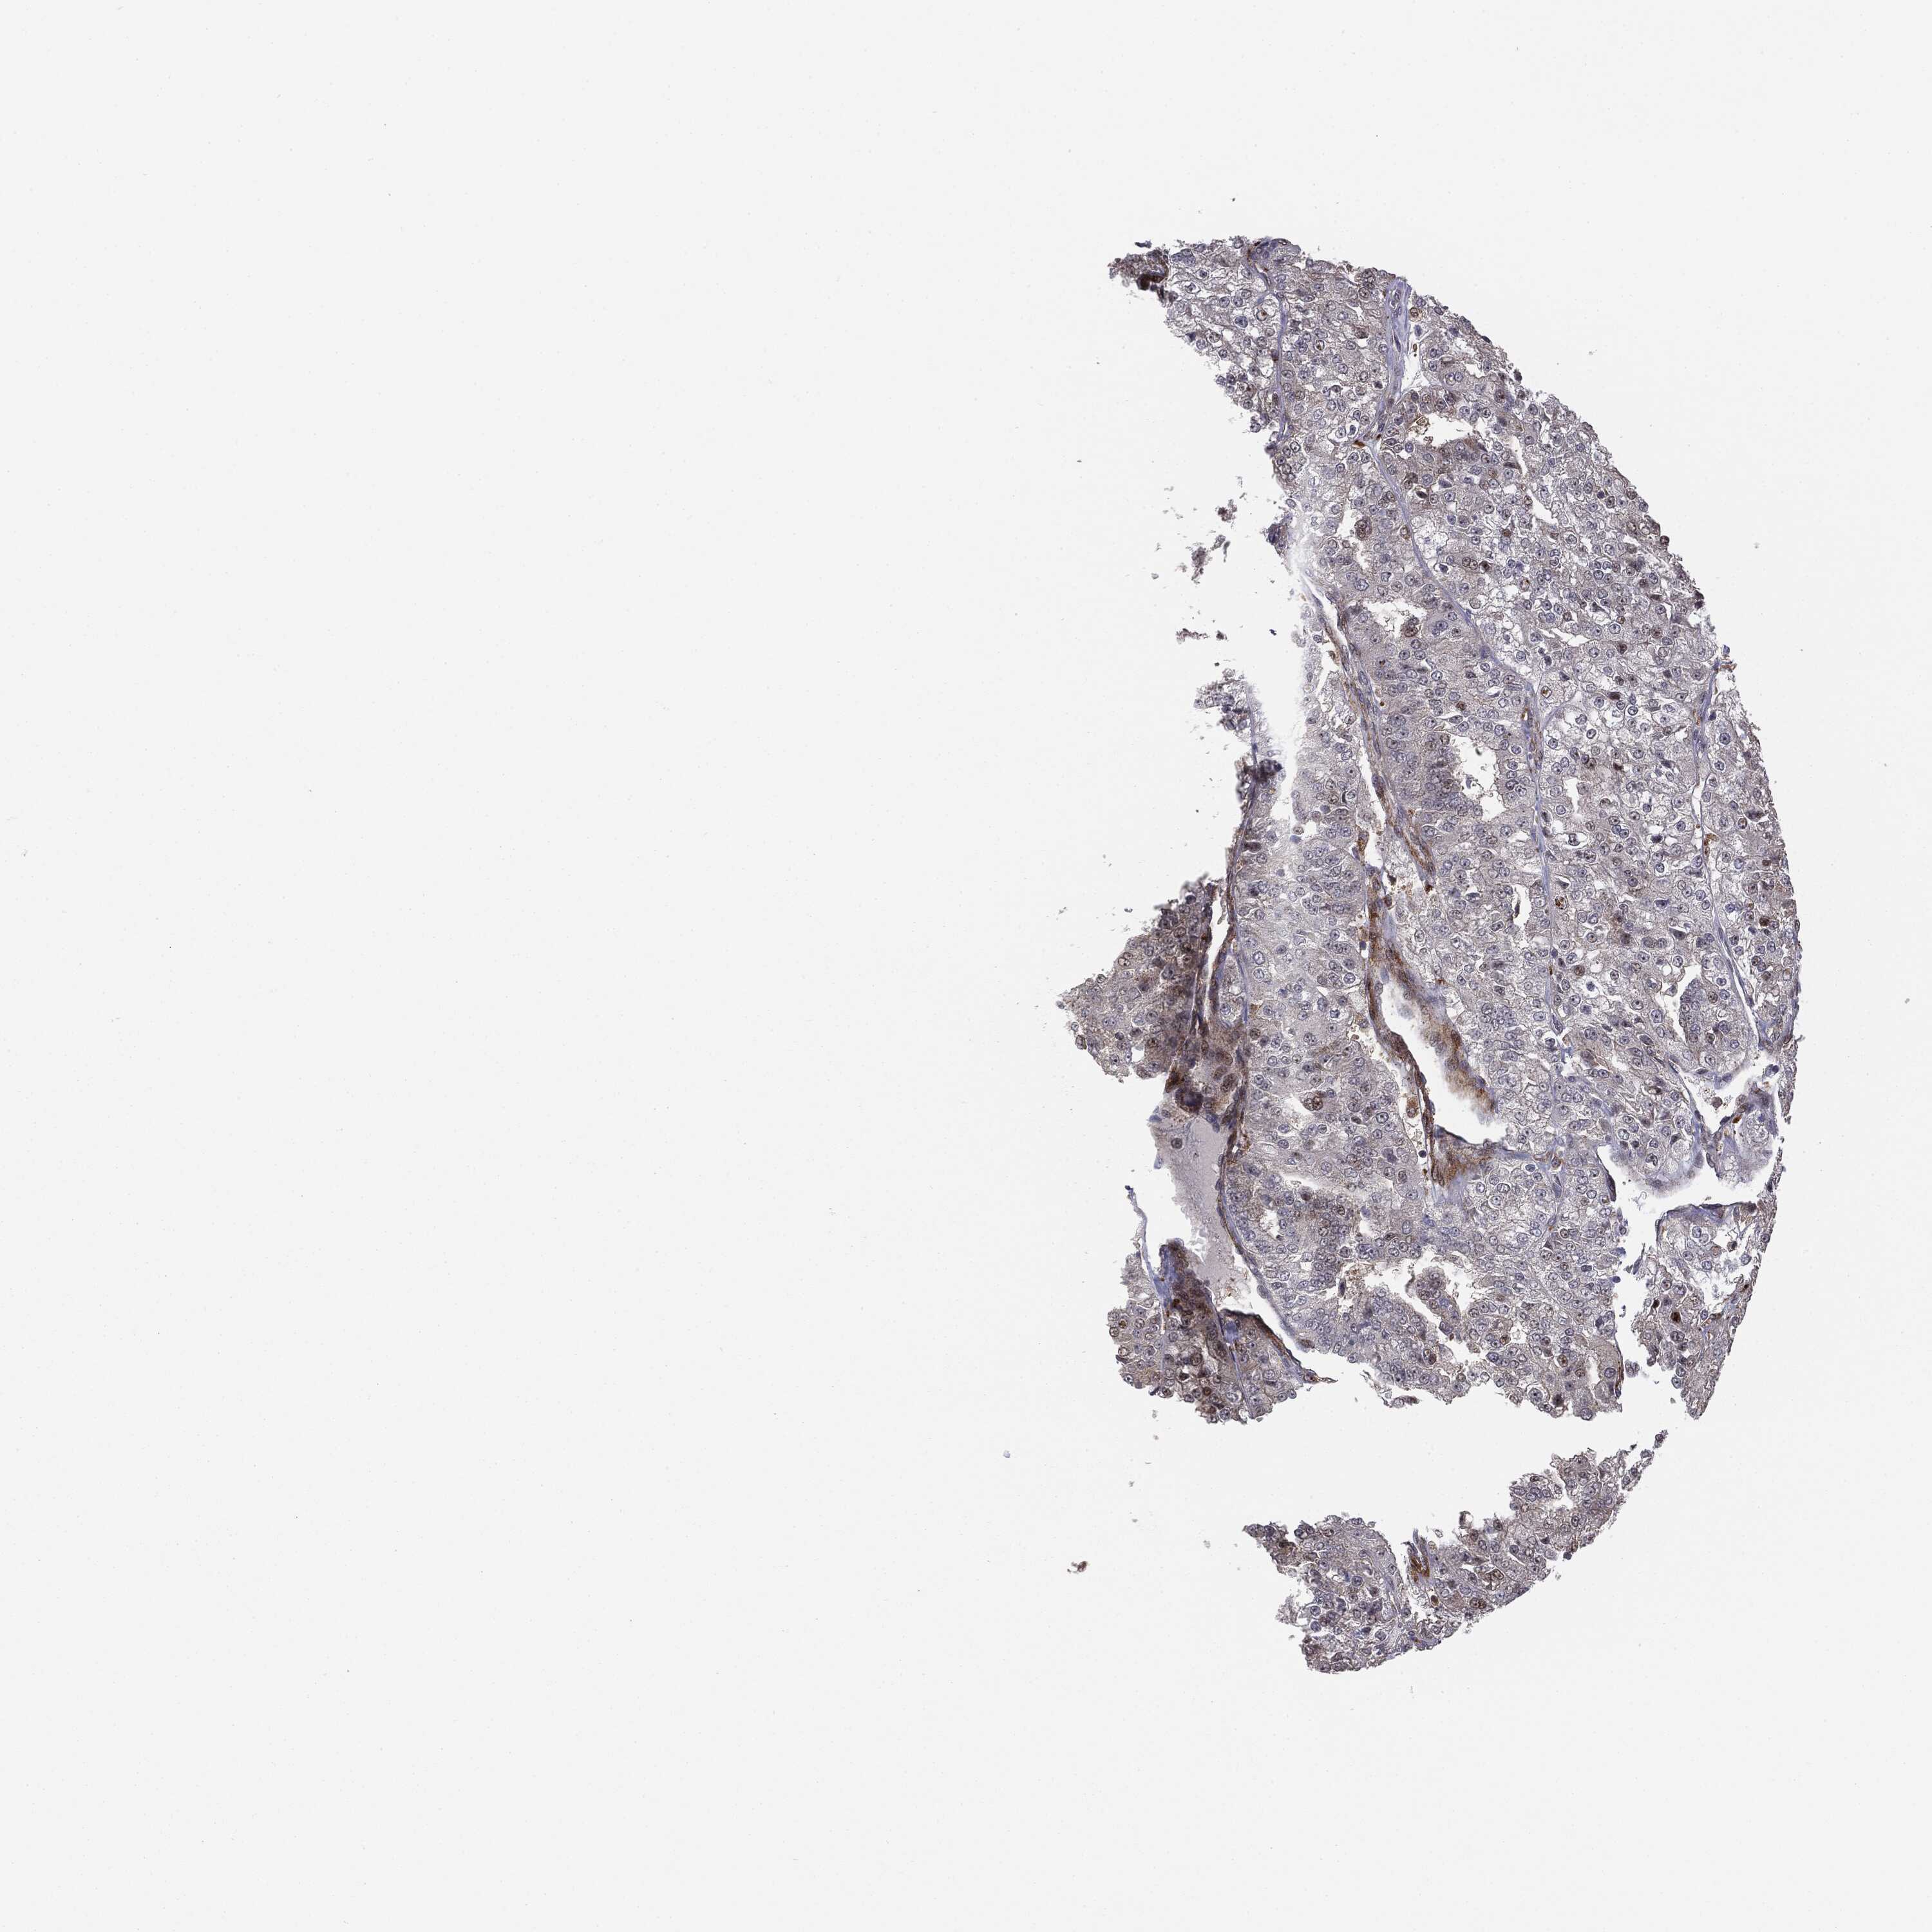

KIDNEY RENAL PAPILLARY CELL CARCINOMA (TCGA) - Interactive survival scatter ploti

The Survival Scatter plot shows the clinical status (i.e. dead or alive) for all individuals in the patient cohort, based on the same data that underlies the corresponding Kaplan-Meier plots. Patients that are alive at last time for follow-up are shown in blue and patients who have died during the study are shown in red.

The x-axis shows the expression levels (FPKM) of the investigated gene in the tumor tissue at the time of diagnosis. The y-axis shows the follow-up time after diagnosis (years). Both axes are complimented with kernel density curves demonstrating the data density over the axes. The top density plot shows the expression levels (FPKM) distribution among dead (red) and alive patients (blue). The right density plot shows the data density of the survived years of dead patients with high and low expression levels respectively, stratified using the cutoff indicated by the vertical dashed line through the Survival Scatter plot. This cutoff is automatically defined based on the FPKM cutoff that minimizes the p-score. The cutoff can be changed by dragging the vertical line or by entering a cutoff value in the square labeled "Current cut-off".

Under the Survival Scatter plot the p-score landscape (black curve; left axis) is shown together with dead median separation (red curve; right axis). Dead median separation is the difference in median mRNA expression between patients who have died with high and low expression, respectively. It is calculated as follows: median FPKM expression of dead patients with high expression - median FPKM expression of dead patients with low expression. This is intended to aid the user in visually exploring custom cutoffs and the associated p-scores and dead median separation.

Individual patient data is displayed and can be filtered by clicking on one or more of the category buttons on the top of the page. Categories describing expression level and patient information include: high, low, alive, dead, female, male and tumor stages. The scale of the x-axis can be toggled between linear and log-scale by clicking on the "x log" button. Mouse-over function shows TCGA ID, patient information and mRNA expression (FPKM) for each patient.

& Survival analysisi

Kaplan-Meier plots summarize results from analysis of correlation between mRNA expression level and patient survival. Patients were divided based on level of expression into one of the two groups "low" (under cut off) or "high" (over cut off). X-axis shows time for survival (years) and y-axis shows the probability of survival, where 1.0 corresponds to 100 percent.

PTEN is not prognostic in Kidney Renal Papillary Cell Carcinoma (TCGA)

Best expression cut offi